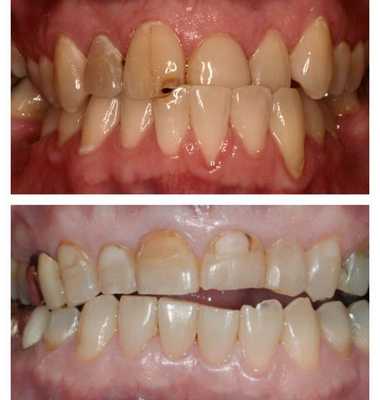

Аномалии структуры твердых тканей

Данные нарушения включают локальную и генерализованную гипоплазию, гиперплазию, несовершенный дентино- и амелогенез. Гипоплазия эмали проявляется наличием симметричных пятен, ямок, бороздок на коронковой части зуба. Дефекты затрагивают все зубы одновременно, могут сочетаться с аномалиями цвета, размеров и формы зубов. Гиперплазия проявляется в форме эмалевых капель, лишних бугорков на жевательных поверхностях зубов; часто протекает совместно с аномалиями окклюзии и положения зубов.

Несовершенный амелогенеза характеризуется появлением желтой или коричневой пигментации, уменьшением толщины эмали, повышенной чувствительностью зубов к температурным, механическим и химическим раздражителям. Данная аномалия зубов иногда сочетается с микродентией, изменением формы зубов.

Несовершенство дентиногенеза затрагивает нарушение развития дентина молочных и постоянных зубов. При аномалии дентина зубы приобретают янтарно-желтый или серовато-коричневый опалесцирующий цвет, быстро стираются, разрушаются и выпадают.

Аномалии цвета

Цвет, блеск и прозрачность эмали относятся к оптическим характеристикам зуба. В норме зубы могут иметь оттенки от бело-голубого до желтого. Считается, что голубоватая эмаль является более хрупкой, а желтоватая - более прочной.

При различных патологических состояниях возможное изменение цвета зубов до розового, серого, коричневого, коричнево-черного, зелено- коричневого, лилового, серо-синего, черного и пр. Патологическая пигментация зубов может иметь вид отдельных пятен или носить диффузный характер.